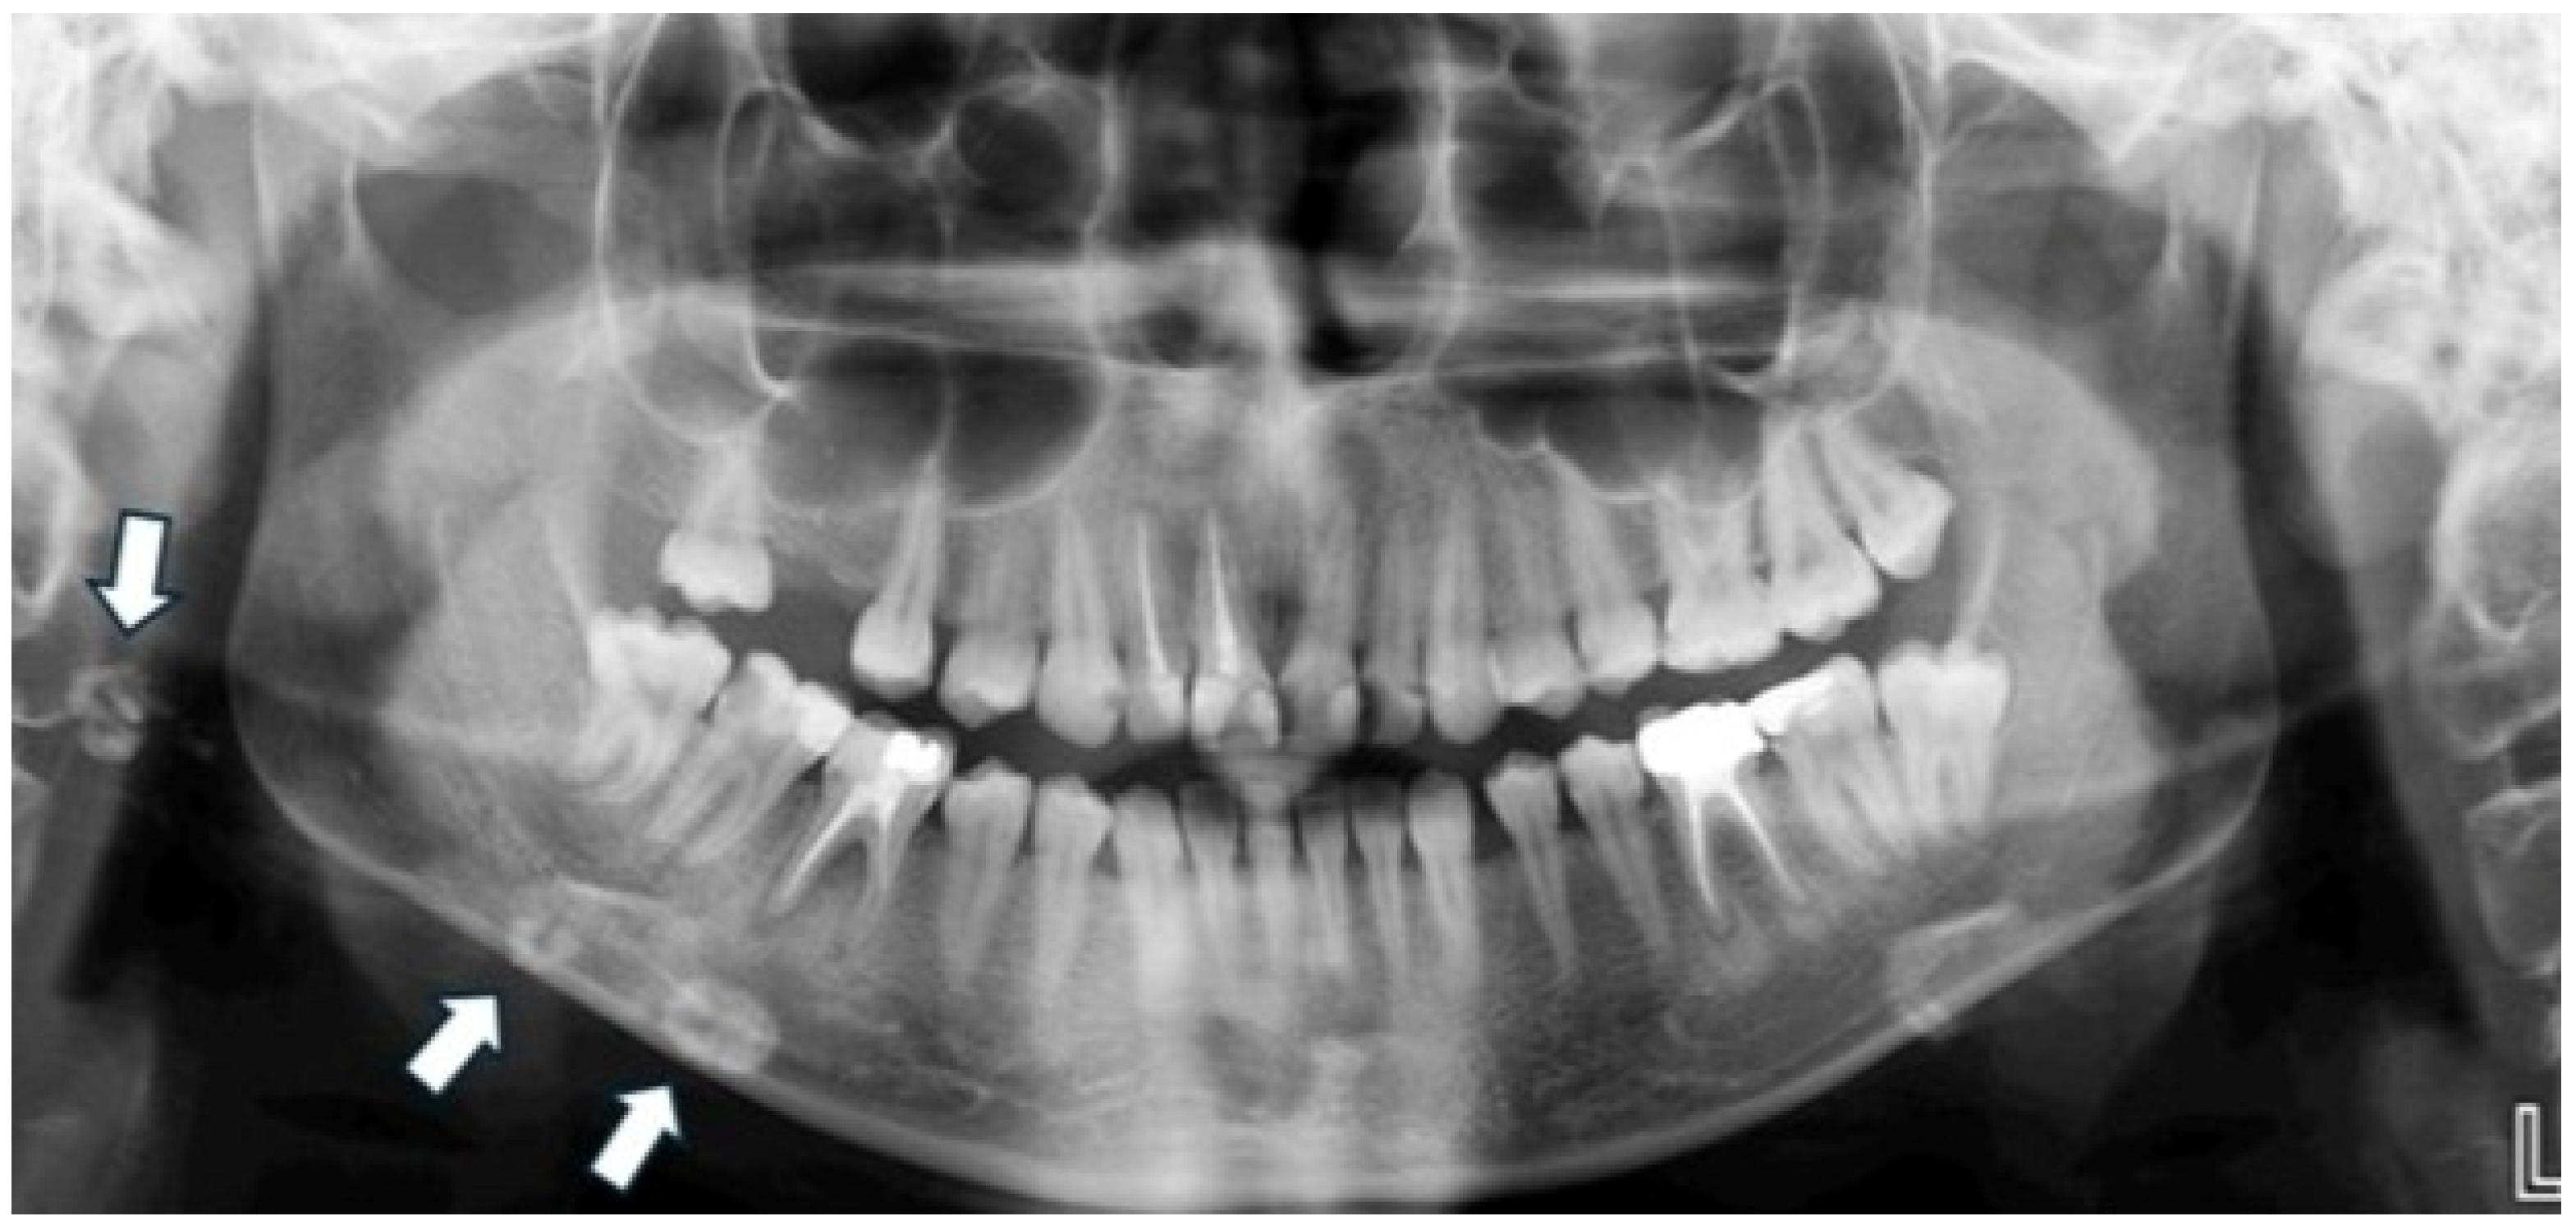

Figure 2. Panoramic radiograph of a 48-year-old male patient demonstrating a unilateral, elongated, and radiopaque structure extending downward from the right temporal region, indicative of styloid ligament calcification.

Regarding the overall frequency of each calcification type among the 122 affected patients, styloid ligament ossification emerged as the most prevalent finding, accounting for 31 cases (25.41%) of all detected anomalies (as visually represented in Figure 2). Conversely, anthrolith was the least frequently encountered, with only two cases (1.64%) identified. Other prominent calcifications included laryngeal cartilage calcification (28 cases, 22.95%), tonsillolith (25 cases, 20.49%, illustrated in Figure 3), calcified lymph node (18 cases, 14.75%, depicted in Figure 4), and calcified atherosclerotic plaque (18 cases, 14.75%). It is pertinent to highlight that a thorough investigation for other commonly reported calcifications/ossifications within the head and neck region, such as arteriosclerosis, phleboliths, and sialoliths, yielded no positive findings throughout our study population.

Stylohyoid ligament ossification proved to be the most common type of calcification/ossification in our study, registering 31 cases, representing 25.41% of all detected anomalies. The styloid process (SP), an approximate 2.5 cm long, thin, cylindrical bony extension projecting downwards from the temporal bone’s pars tympanica, is anatomically situated between the carotid arteries and the internal jugular vein, anteromedial to the stylomastoid foramen and posterior to the tonsillar fossa. The “stylohyoid complex” refers to the anatomical unit formed by the SP, the stylohyoid ligament, and the lesser horn of the hyoid bone.